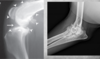

Describe the shoulder joints on radiography.

Remember Clavicles in cats, and Sometimes rudimentary ones seen in large dogs, they look like poorly mineralized structures. Calcified opacities around or within the shoulder joint are commonly seen, majority of them are incidental findings though. NB The Supraglenoid tubercle's physis in immature dogs, can be misidentified as fracture.

identify

NB The Supraglenoid tubercle's physis in immature dogs, can be misidentified as fracture. (left image) rudimentary clavicle in right image